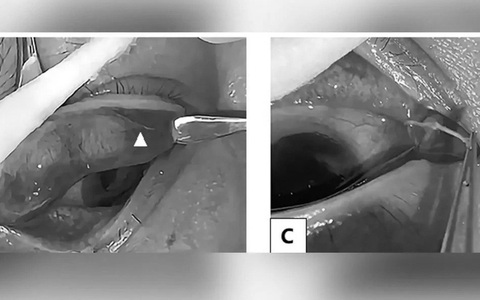

Tuy hiếm gặp nhưng nhiều người đã phải cắt phổi vì nang sán dây chó gây khối u trong phổi. Nang sán dây chó hay gặp ở gan, sau đó là phổi và các cơ quan khác như thận, lách, tim, tổ chức thần kinh hoặc xương...